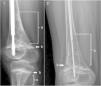

Paciente diagnosticado de osteogénesis imperfecta (OI) tipo VI, portador de mutación compuesta en SERPINF1 (c.1271-279dupl + [907C>T]; p.[Ala91_Ser93dup] + [Arg303*]). A la edad de 9 años y 8 meses, tras mala respuesta a bifosfonatos, inicia tratamiento con denosumab. Pasados 3 meses, observamos la aparición de una banda hiperdensa en ambas metáfisis femorales, con extensión en sentido craneal en forma de patrón difuso de esclerosis que asemeja la imagen de una «nube de humo». Tras 4 años de tratamiento, el ratio de fracturas no ha aumentado y no hemos observado cambios significativos en la imagen previamente descrita (fig. 1).

Durante el crecimiento, la administración intravenosa de BF da lugar a la aparición de la clásica imagen radiológica en «líneas cebra». Denosumab incrementa la formación ósea generando una banda hiperdensa a nivel de la metáfisis3, sin embargo esta imagen en patrón difuso no había sido descrita con anterioridad, siendo quizás una expresión fenotípica relacionada con mutación específica que porta nuestro paciente.